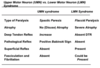

What are signs of a lower motor neurone lesion?

- Hypotonia: due to loss of muscle activation

- Areflexia: no LMN to complete reflex arc

- Dennervation Muscle atropy: LMN supplies trophic factors to muscle so lost

- Fasiculations:due to upregulation of muscle nAChRs to try to compensate for denervation

- Weakness/Flaccid paralysis

- Fibrillations

- Weakness: dennervation

What are signs of an upper motor neurone lesion?

- Hypertonia: loss of descending inhibition by inhibitory interneurones

- Spasticity: LMN still in tact but no inhibition

- Hyperreflexia: still LMN

- Clasp Knife rigidity: golgi tendon reflex

- Weakness

- Disue atropy not due to loss of trophic factors

- Babinski’s reflex (Extensor plantar response)

- Acute flaccid paralysis: spinal shock